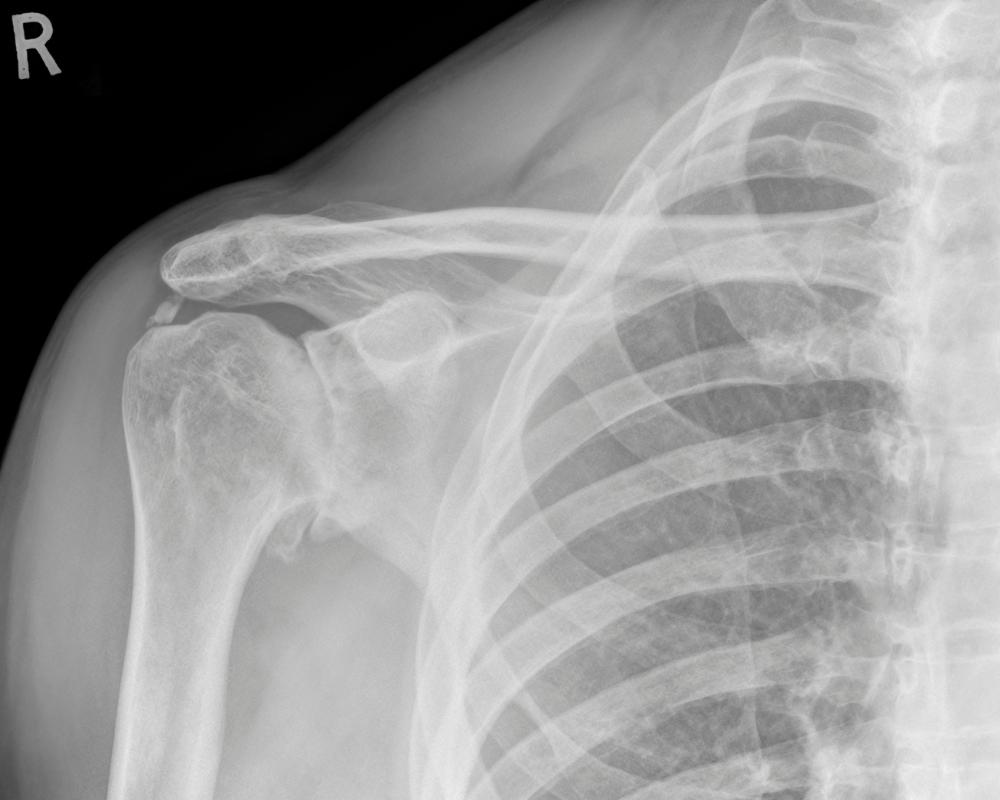

Thoái hóa khớp vai là bệnh lý mãn tính xảy ra khi hai đầu xương cánh tay nối với xương bả vai bị mài mòn, không còn bao bọc được đầu xương, khiến cho các đầu xương cọ xát với nhau gây viêm, đau. Bệnh thoái hóa khớp vai gây ra những bất tiện và ảnh hưởng đến khả năng cầm nắm, vận động và sinh hoạt hàng ngày.

Nguyên nhân chủ yếu gây nên bệnh thoái hóa khớp vai xuất phát từ quá trình lão hóa tự nhiên của cơ thể, chấn thương thể thao tại khu vực bả vai, thường xuyên hoạt động bả vai với tần suất cao… Hiện nay thoái hóa khớp vai trở nên rất phổ biến và có xu hướng trẻ hóa ở những người từ 20 - 30 tuổi.